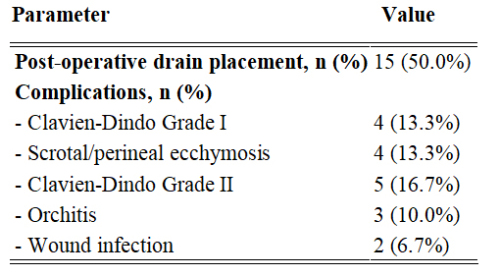

Kenan Yalçın, Engin Kölükçü

Webbed penis is a congenital anomaly in which a fold of

skin extends from the scrotum to the ventral surface of the penile

shaft, obscuring the penoscrotal angle []. It is most commonly

identified during infancy or at the time of circumcision. This

condition may result in a visually shortened penis and is

recognized as a frequent cause for delayed circumcision [].

Performing circumcision without correcting the web can lead to

downward urine flow during childhood and may impair sexual

function in adulthood. Therefore, surgical correction of the web

is generally considered mandatory prior to circumcision [].

However, correcting the web post-circumcision is often more

challenging due to the loss of preputial tissue.

In Turkey, circumcision is a nearly universal practice

performed for cultural and religious reasons. In some cases, it

is carried out by non-specialist practitioners, which may lead

to underdiagnosis of such anomalies [,]. Numerous studies

have investigated the surgical correction of primary webbed

penis [,-]. The main goal of treating penoscrotal webbing is

to elongate the ventral penile skin by transecting the web. This

is traditionally achieved using a transverse incision followed

by vertical closure—commonly referred to as the Heineke-

Mikulicz technique []. Other surgical methods have also been

introduced, including V-Y plasty, Z-plasty, lateral parapenile

incisions, and preputial flap rotation [].

The present study aims to compare the clinical outcomes

of Heineke-Mikulicz and V-Y scrotoplasty techniques in the

surgical correction of penoscrotal webbing in pediatric patients

with varying grades of severity.